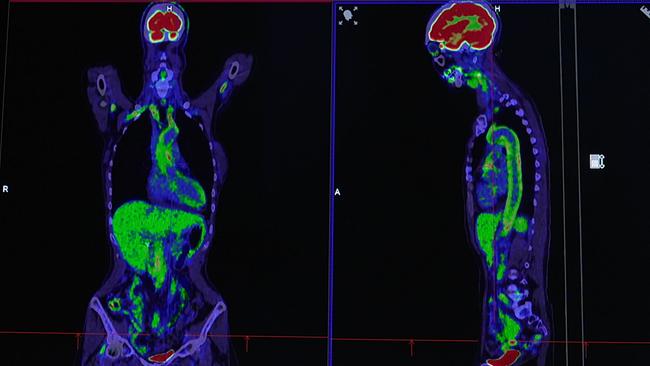

Selten, aber gefährlich – Gefäßentzündung „Riesenzellarteriitis“

Riesenzellarteriitis ist eine chronische Entzündung der großen und mittelgroßen Arterien, die vor allem bei älteren Menschen, häufiger bei Frauen, auftritt.

Sie gilt als seltene Erkrankung. In Österreich sind ca. 1.500 bis 1.900 Menschen betroffen. Riesenzellarteriitis kann akut starke Kopf- und Kieferschmerzen verursachen, bei unzureichender Behandlung kann es in weiterer Folge auch zu einem Schlaganfall und Sehverlust kommen. Die genaue Ursache für die Erkrankung ist bisher unbekannt, es wird jedoch angenommen, dass eine Fehlsteuerung des Immunsystems

eine Rolle spielt. Diese führt zu einer Entzündung der Gefäßwände, die den Blutfluss beeinträchtigen - im Extremfall droht eine Blutunterversorgung.